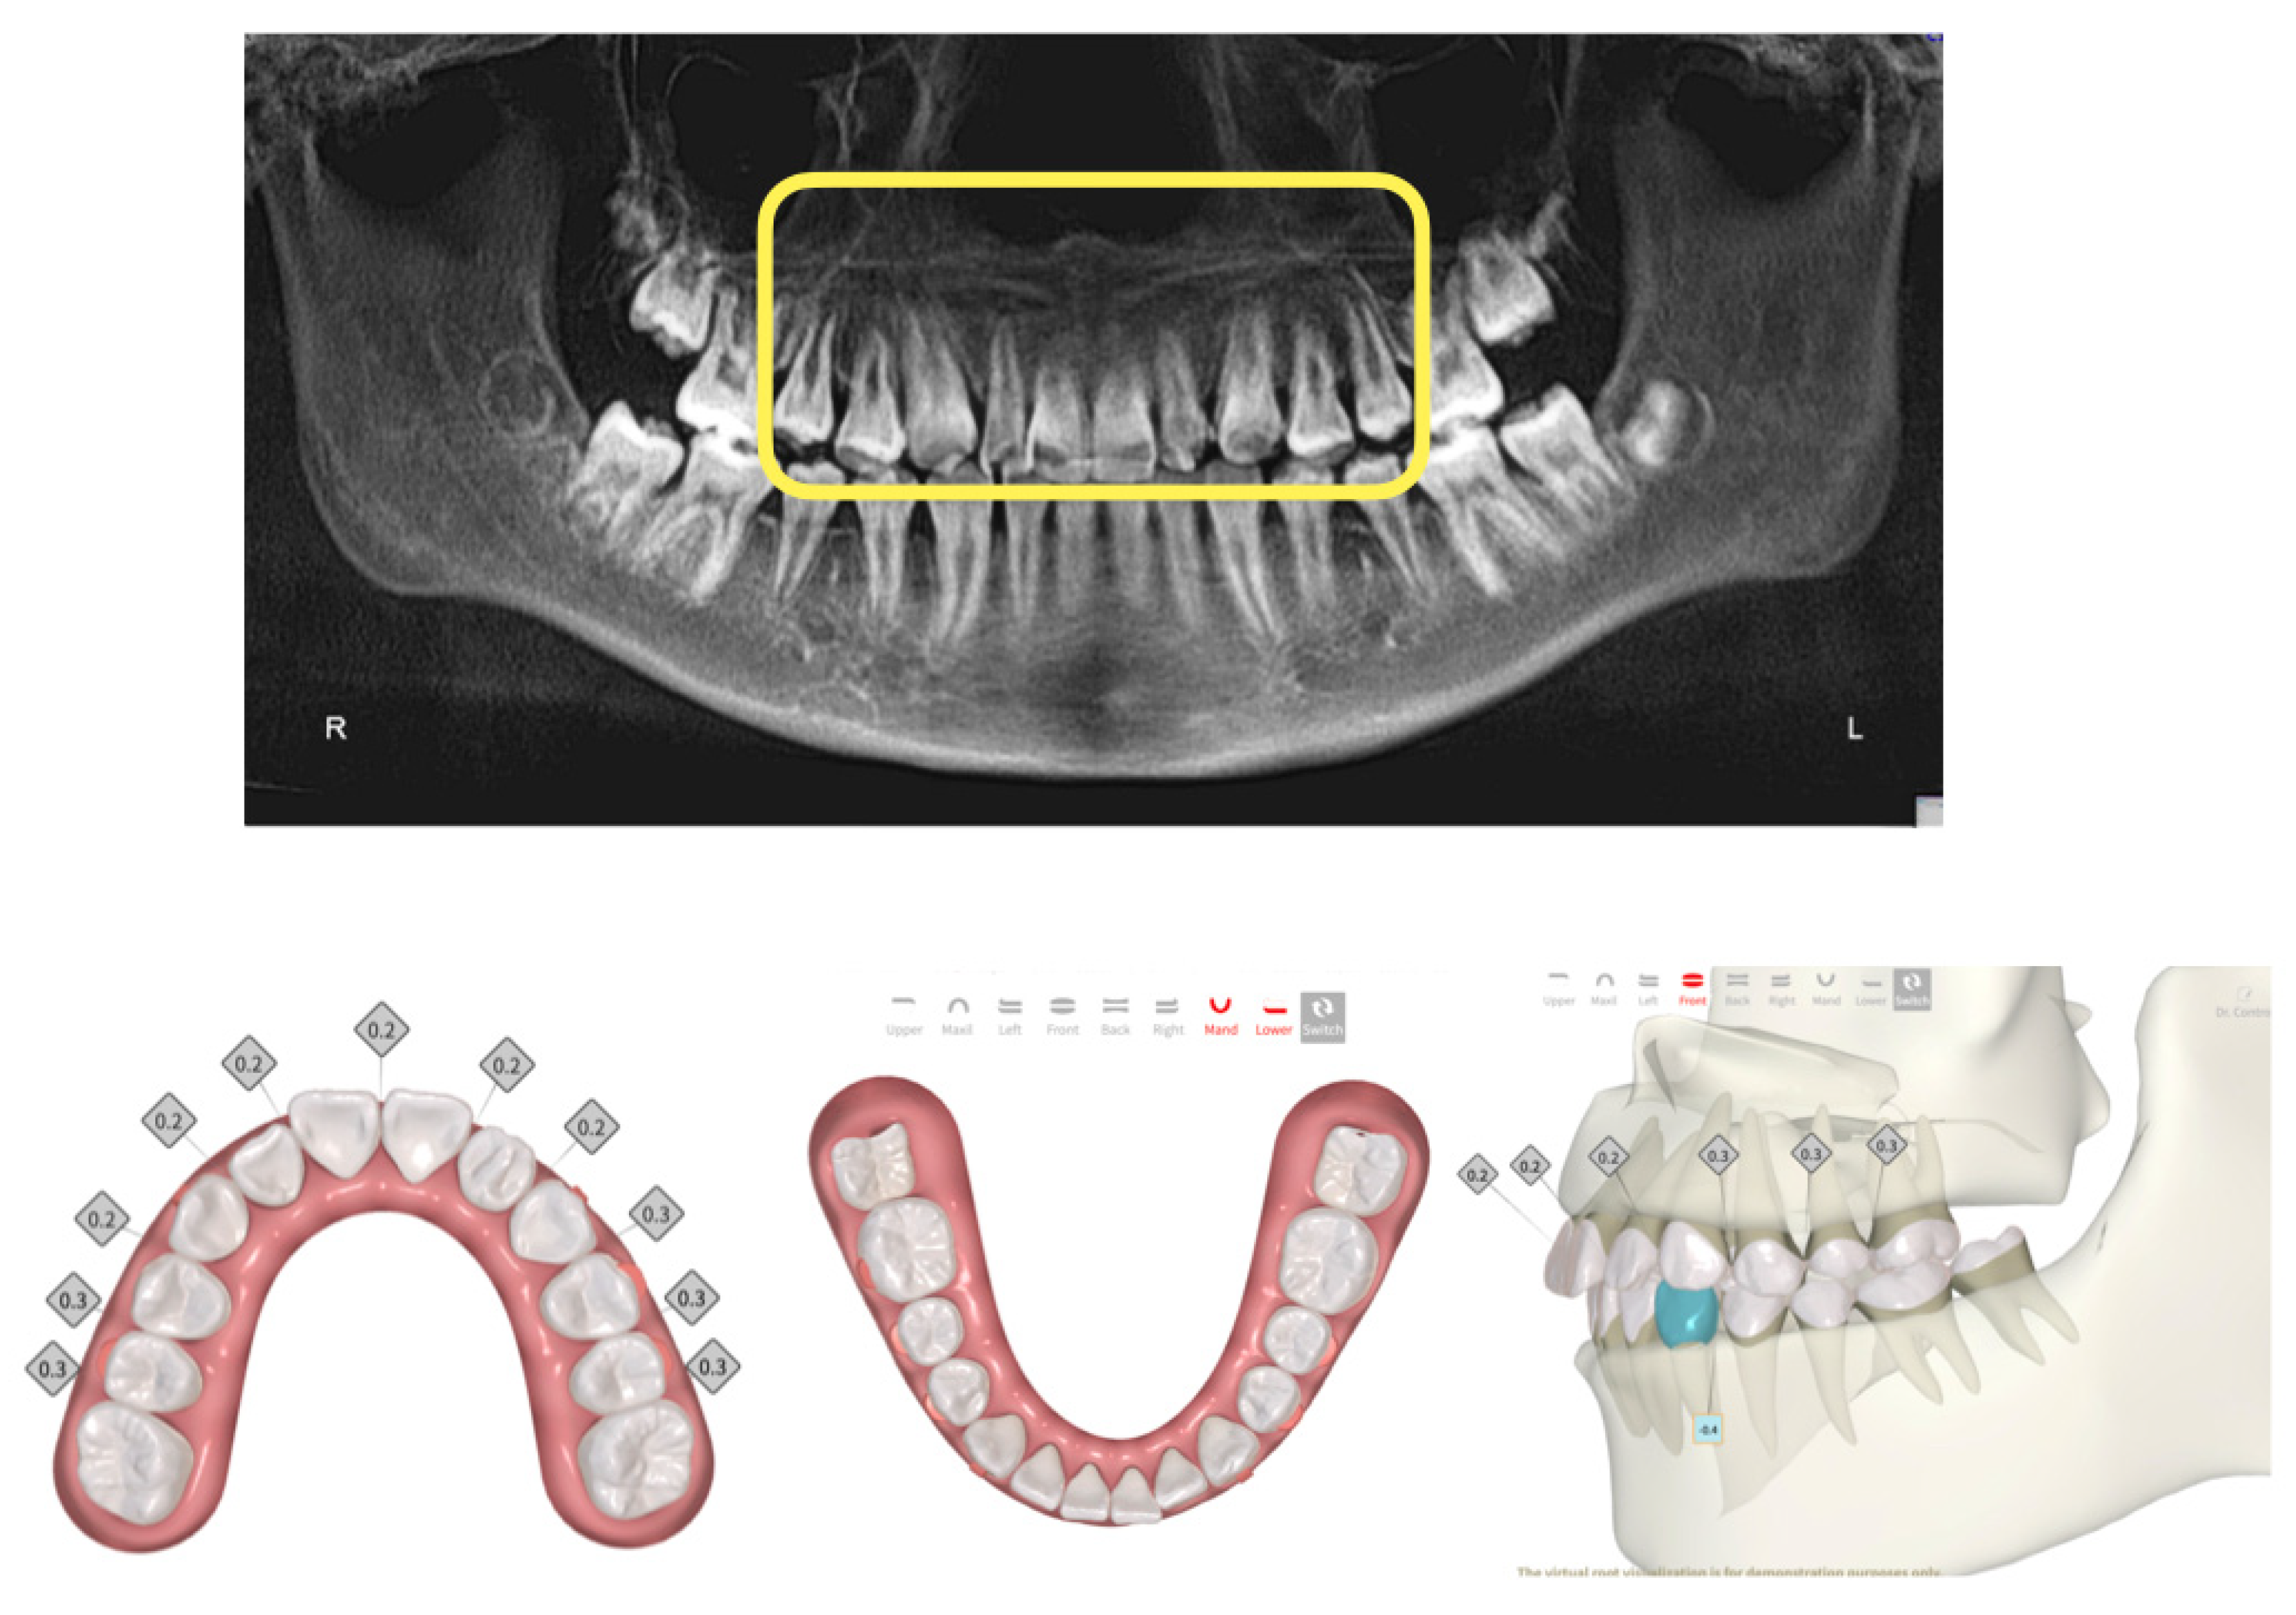

Orthodontic News - OrthoFXTM Announces Nationwide。Orthodontic Aligners: Current Perspectives for the Modern。What's New in Aligners for 2024 | Orthodontic Products。Full article: Clear aligners generations and orthodontic。。「アライナージェネレーション Alignergeneration : Dr. 尾島賢治のテクニック&分析ポイント131のすべて」尾島賢治 / 檀 知里 / 渡邉仁資 / 熊谷友理子定価: ¥29,700(税込)